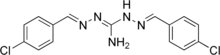

| Formula | C15H13Cl2N5 |

| Molar mass | 334.20 g·mol−1 |